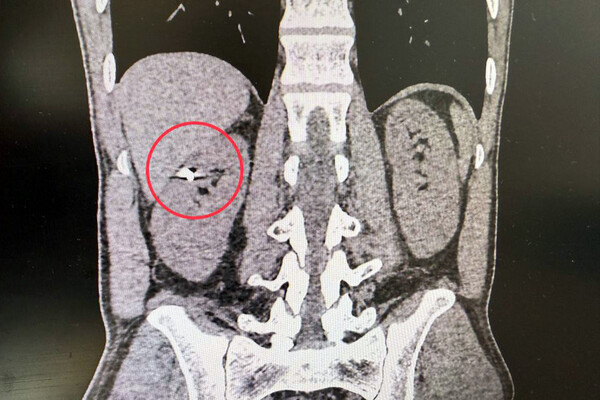

35-летний пациент получил травму около года назад, кусок металла размером 1 см прошел через печень и вонзился ему в почку. В ходе обследования медики обнаружили инородное тело в паренхиме – части органа, который фильтрует кровь. Было принято решение о проведении хирургического вмешательства.

«По данным компьютерной томографии, мы зафиксировали осколок в верхней части правой почки. Печень была тесно припаяна к почке, и извлечение осколка могло привести к серьезному кровотечению и потере органа. Мы сделали резекцию почки, причем лапароскопическим методом, и извлекли осколок», — рассказал заведующий урологическим отделением больницы Селим Везирханов.